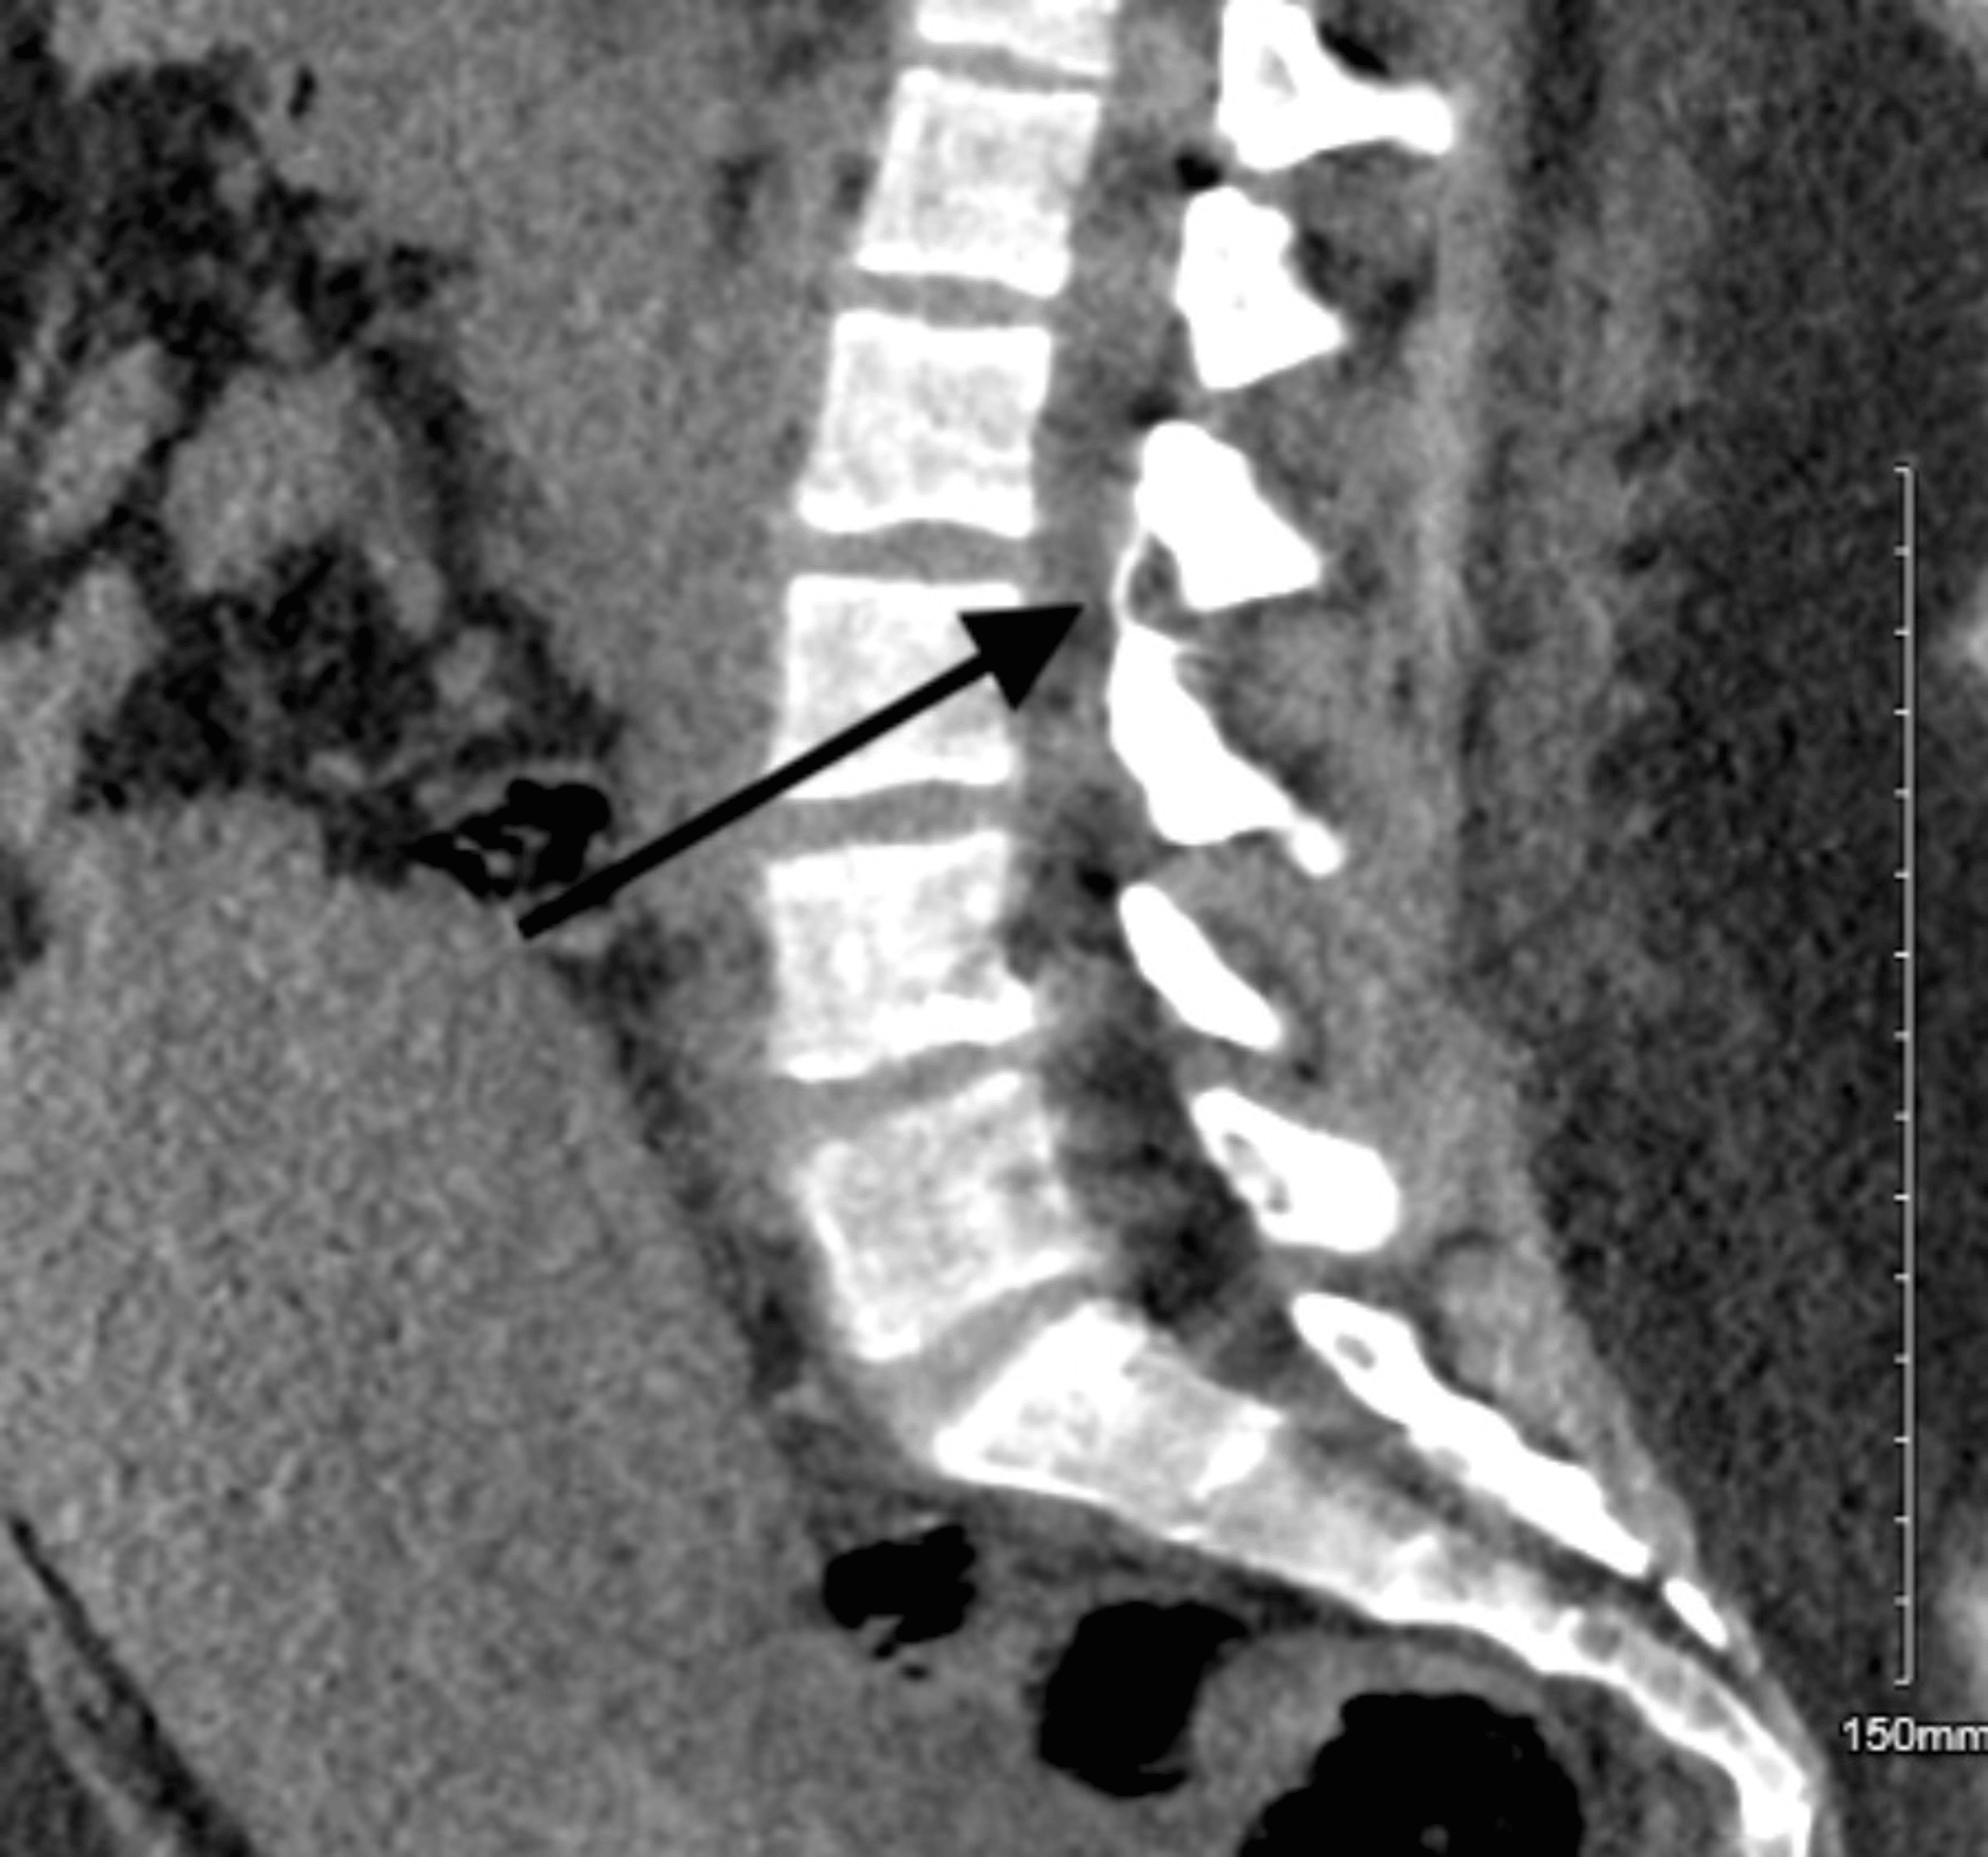

Computed tomography scan and resonance imaging showing Epidural Catheter Broke Off In Back Visualization of retained catheter is difficult. Catheter breakage is a recognised complication of epidural anaesthesia, often attributed to trauma on insertion or excessive. The epidural catheter was localized in the right paraspinal gutter and pulled out by using a blunt nerve hook. Hence, the decision was taken to remove the catheter, but as the catheter was being pulled off along. Epidural Catheter Broke Off In Back.